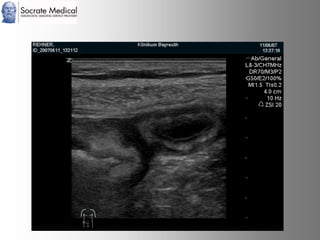

Il documento presenta la tecnologia della zone sonography, che promette una rivoluzione nel campo degli ultrasuoni, superando i limiti dei sistemi tradizionali grazie a metodi di acquisizione dati più veloci e una gestione delle informazioni migliorata. Questa tecnologia consente una maggiore definizione dell'immagine, una riduzione degli artefatti e un'ottimizzazione del processo diagnostico, con vantaggi in termini di tempo e costi. Inoltre, il channel domain processing e la zone speed technology offrono applicazioni avanzate e miglioramenti nella sicurezza diagnostica.